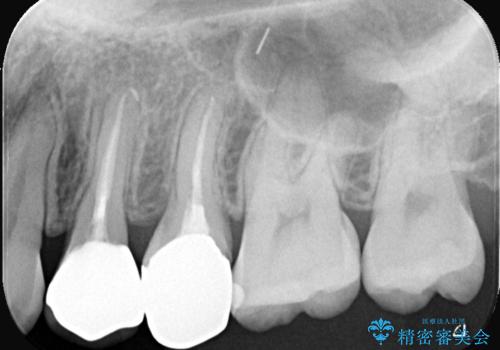

- 「銀歯があるとお口の中が気持ち悪い感じがするので、セラミックに変えたい」を主訴に来院された患者様です。

銀歯と虫歯を除去し、オールセラミッククラウンで治療を行いました。

銀歯の下は虫歯になっていました。 根管治療は希望されなかったため、虫歯を除去後、被せ物のみオールセラミックで治療を行いました。